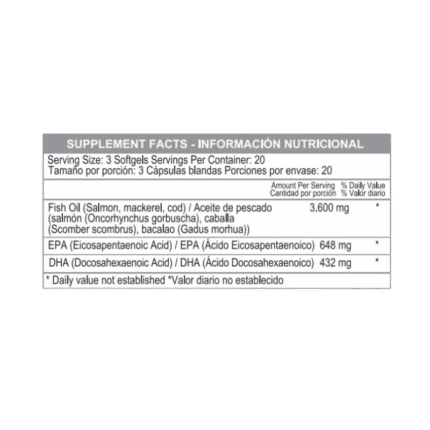

Potente mezcla de ácidos grasos esenciales Omega 3, 6 y 9 con 1200 mg por cápsula. Contribuye a la salud cardiovascular, cerebral y de la piel. Ideal para quienes buscan bienestar integral y nutrición completa en una sola cápsula diaria

El Triple Omega 369 es una combinación esencial de ácidos grasos que apoya funciones vitales del cuerpo. Esta fórmula proporciona los beneficios del Omega 3, 6 y 9, esenciales para mantener una buena salud.